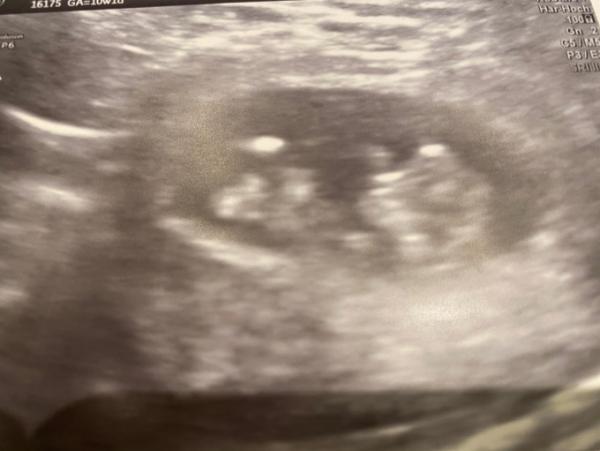

Huhu ihr Lieben! nach unserem Schrecken am Sonntag mit der Blutung, sagte heute die Ärztin, dass alles perfekt entwickelt ist und wir ein Super-Baby haben. Es schluckt schon, der Magen war gefüllt und Nacken und Gesichtslinie sind schon gut zu erkennen. Herzchen schlägt . Was will man mehr so kurz vor Weihnachten? Schöne Zeit für euch!

Und es wurde in 10+1 über den Bauch geschallt, da war ich überrascht!